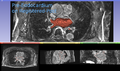

We extract the left atrium endocardium region (blood pool) from the DEMRI image using a multi-atlas based scheme. In Figure E1, Figure E2, and Figure E3 below, we show the current segmentation results.

In the left image below (Figure R2), the manual segmentation of the endo-cardium is overlaid on the pre-op MRI. In the right image below (Figure R3), the same manual segmentation of the endo-cardium (of the pre-op MRI) is overlaid on the registered post-op MRI. This shows the registration accuracy around the endo-cardium region, which is the region of interest.